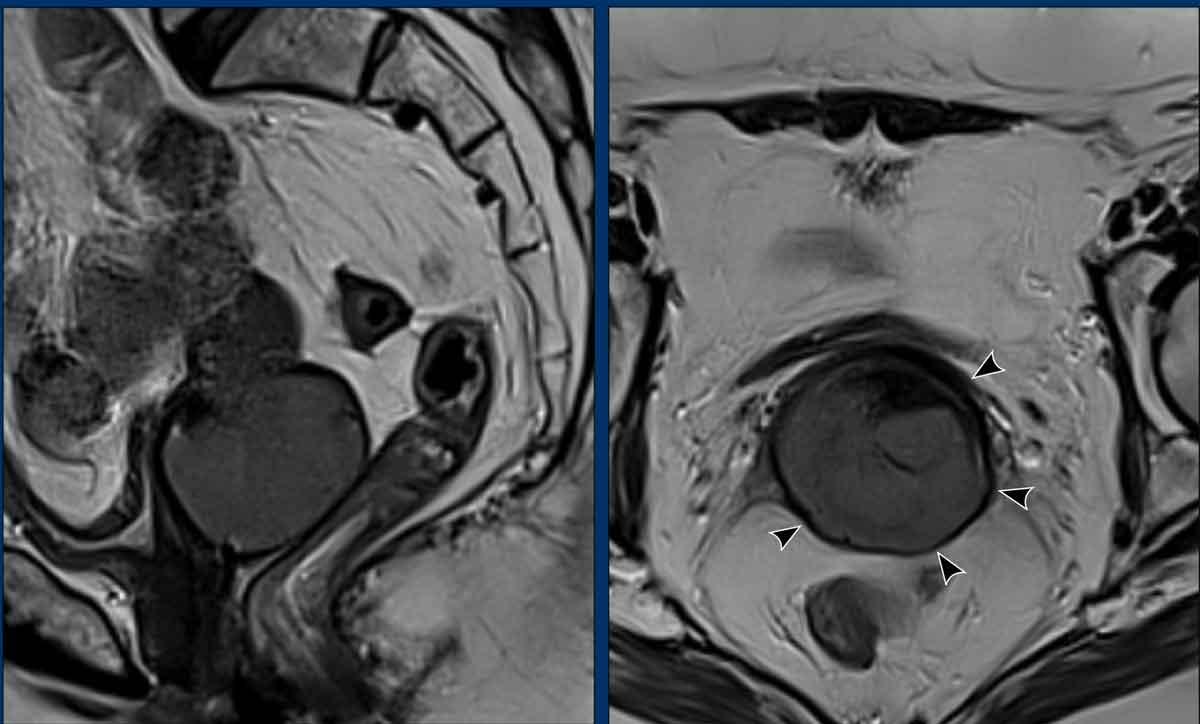

Khi vòng mô đệm giảm tín hiệu của cổ tử cung còn nguyên vẹn (hình bên trái), MRI có thể dự đoán sự vắng mặt của xâm lấn cạnh cổ tử cung với giá trị tiên đoán âm cao hơn 90%.

Sự gián đoạn của vòng mô đệm giảm tín hiệu của cổ tử cung (hình bên phải) và tín hiệu khối u hoặc khối mô mềm lan rộng vào vùng cạnh cổ tử cung là các dấu hiệu gợi ý xâm lấn cạnh cổ tử cung (giai đoạn FIGO IIB).

Bẫy chẩn đoán

– Giãn rộng so với xâm lấn

Ví dụ này cho thấy một khối u lớn làm giãn rộng cổ tử cung.

Lưu ý rằng không có xâm lấn thực sự vào vùng cạnh cổ tử cung vì vòng mô đệm giảm tín hiệu của cổ tử cung hoàn toàn còn nguyên vẹn như được chỉ ra bởi các đầu mũi tên.